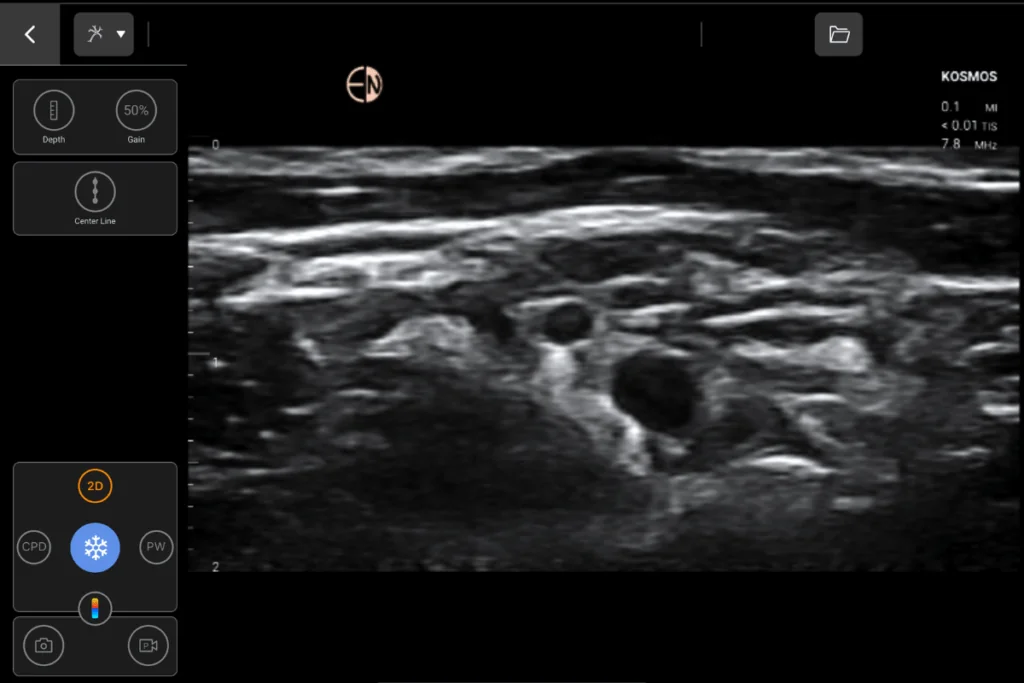

Excellent Image Resolution

Kosmos no-compromise image quality provides detailed anatomical information for procedural user and peri-operative assessments

Compound imaging on the Lexsa probe provides improved visualization of the anatomy and needle path

Lexsa Linear Array probe for MSK, Vascular, Nerve, Guidance and Lung applications